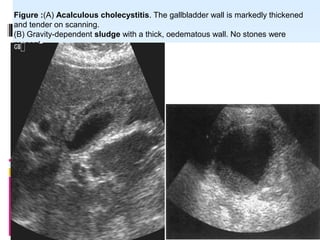

ACALCULUS CHOLECYSTITIS

 Acute acalculous cholecystitis (AAC) refers

development of cholecystitis either in a gallbladder without

gallstones or in a gallbladder with gallstones where the

stones are not the contribuatry factor to the development

of cholecystitis .

AETIOLOGY

 It usually occurs in critically ill or

 injured patients.

Figure :(A) Acalculous cholecystitis. The gallbladder wall is markedly thickened

and tender on scanning.

(B) Gravity-dependent sludge with a thick, oedematous wall. No stones were

present.